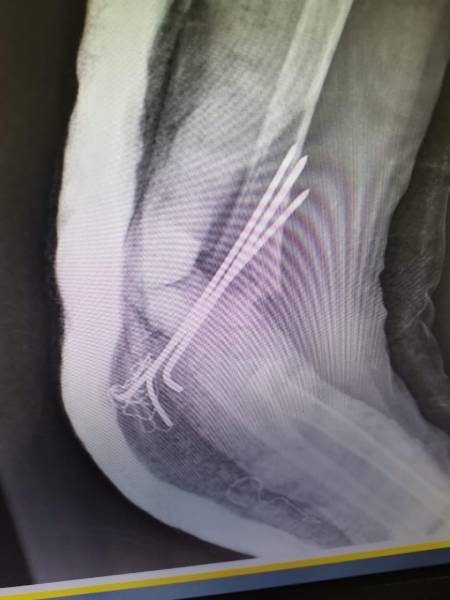

- إجراء عمليات جراحية معقدة و دقيقة في مجال العظام و المفاصل و الكسور و الإصابات ، رغم الضغط الكبير على المستشفى و أعداد المراجعين الكبيرة.

- تطبيق تقنيات جراحية حديثة و متقدمة، و ذلك في ظل التحديات التي يواجهها الفريق بسبب أعداد المرضى و المراجعين الكبيرة.